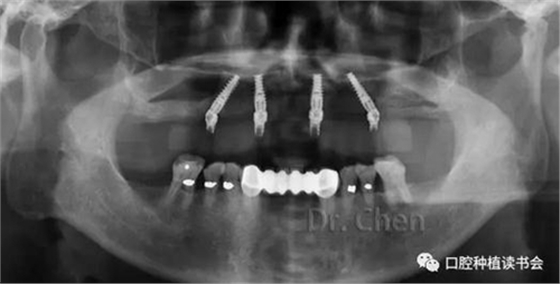

必要時(shí)用記號筆標(biāo)注便于技師調(diào)改(圖7),必要時(shí)拍攝曲面斷層片(圖8),可見所有基臺(tái)臨時(shí)套筒完全就位。

▲ 試戴樹脂牙就位后拍攝曲斷片